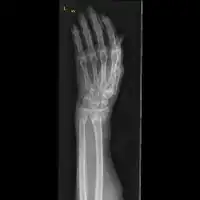

The diagnosis of a forearm fracture is made by first inspecting and then feeling the injured forearm for any obvious deformity and tenderness, with particular attention to the radial head.[2] The type of forearm fracture can be confirmed by an x-ray, usually with views from the front and the side, and must include the wrist and elbow joints.[2]

Front view of displaced fractured radius and ulna at wrist

Side view of displaced fractured radius and ulna at wrist